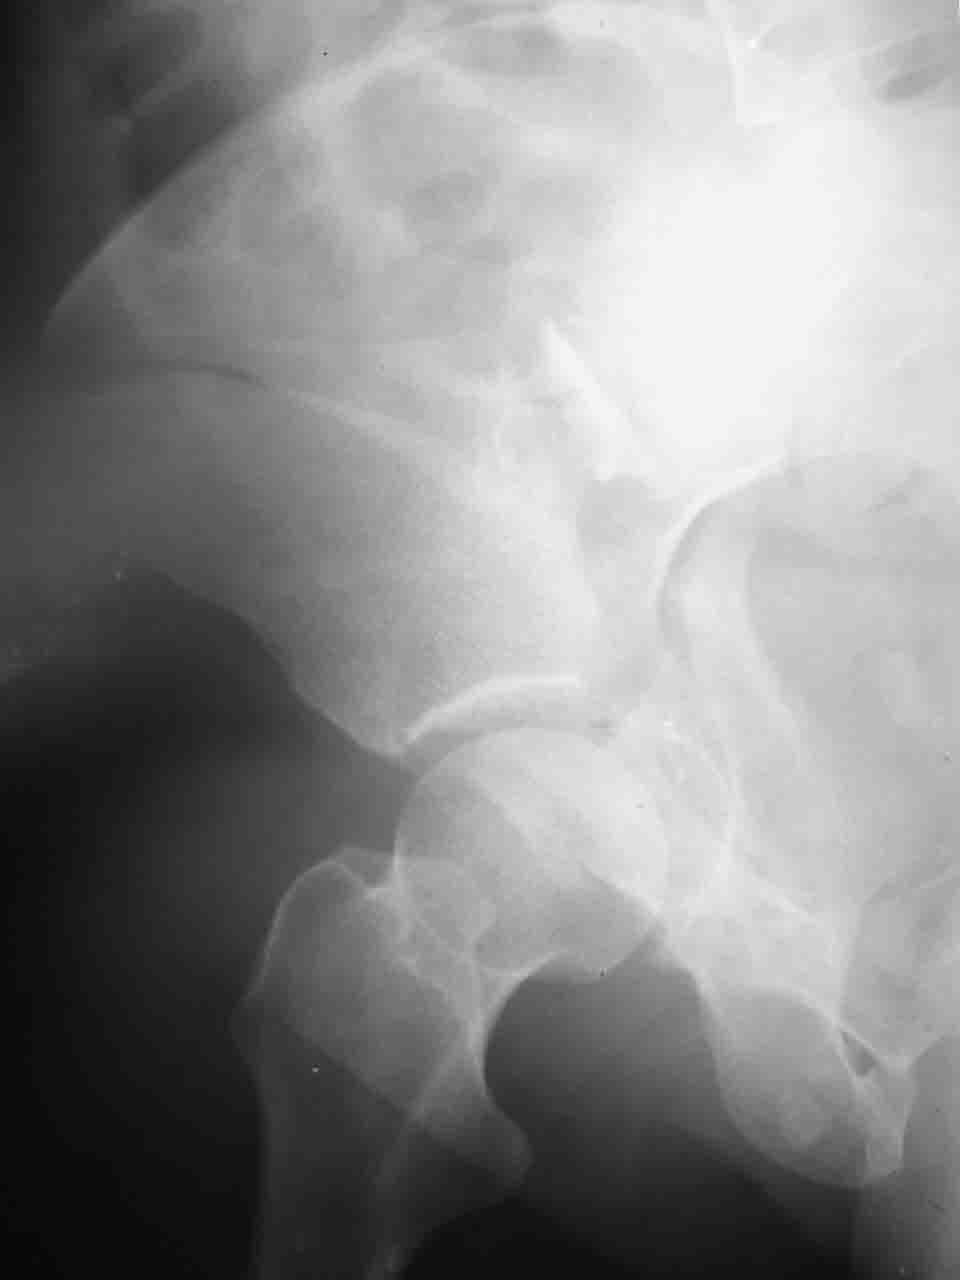

Снимки и схема